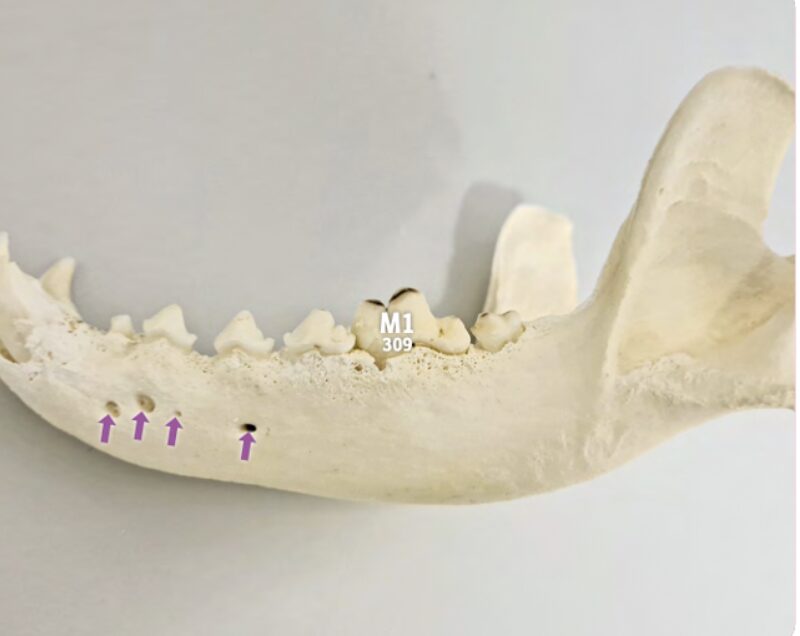

Foramen mentale: Verwechselungsgefahr beachten

Unter dem Foramen mentale versteht man die Austrittslöcher der Mentalnerven im Unterkieferknochen. Beim Hund können sie in variabler Anzahl von 1 bis 6 vorhanden sein.

Auf dem Röntgenbild zeigt sich eine Aufhellung durch das Foramen mentale (dicke Pfeile), die normal ist. Wichtig zu wissen: Foramina mentalia können sich manchmal mit der Wurzel überlagern. Achten Sie darauf, das Foramen mentale nicht mit einer Zyste, einem Wurzelgranulom oder einer Osteolyse in Wurzelnähe zu verwechseln.